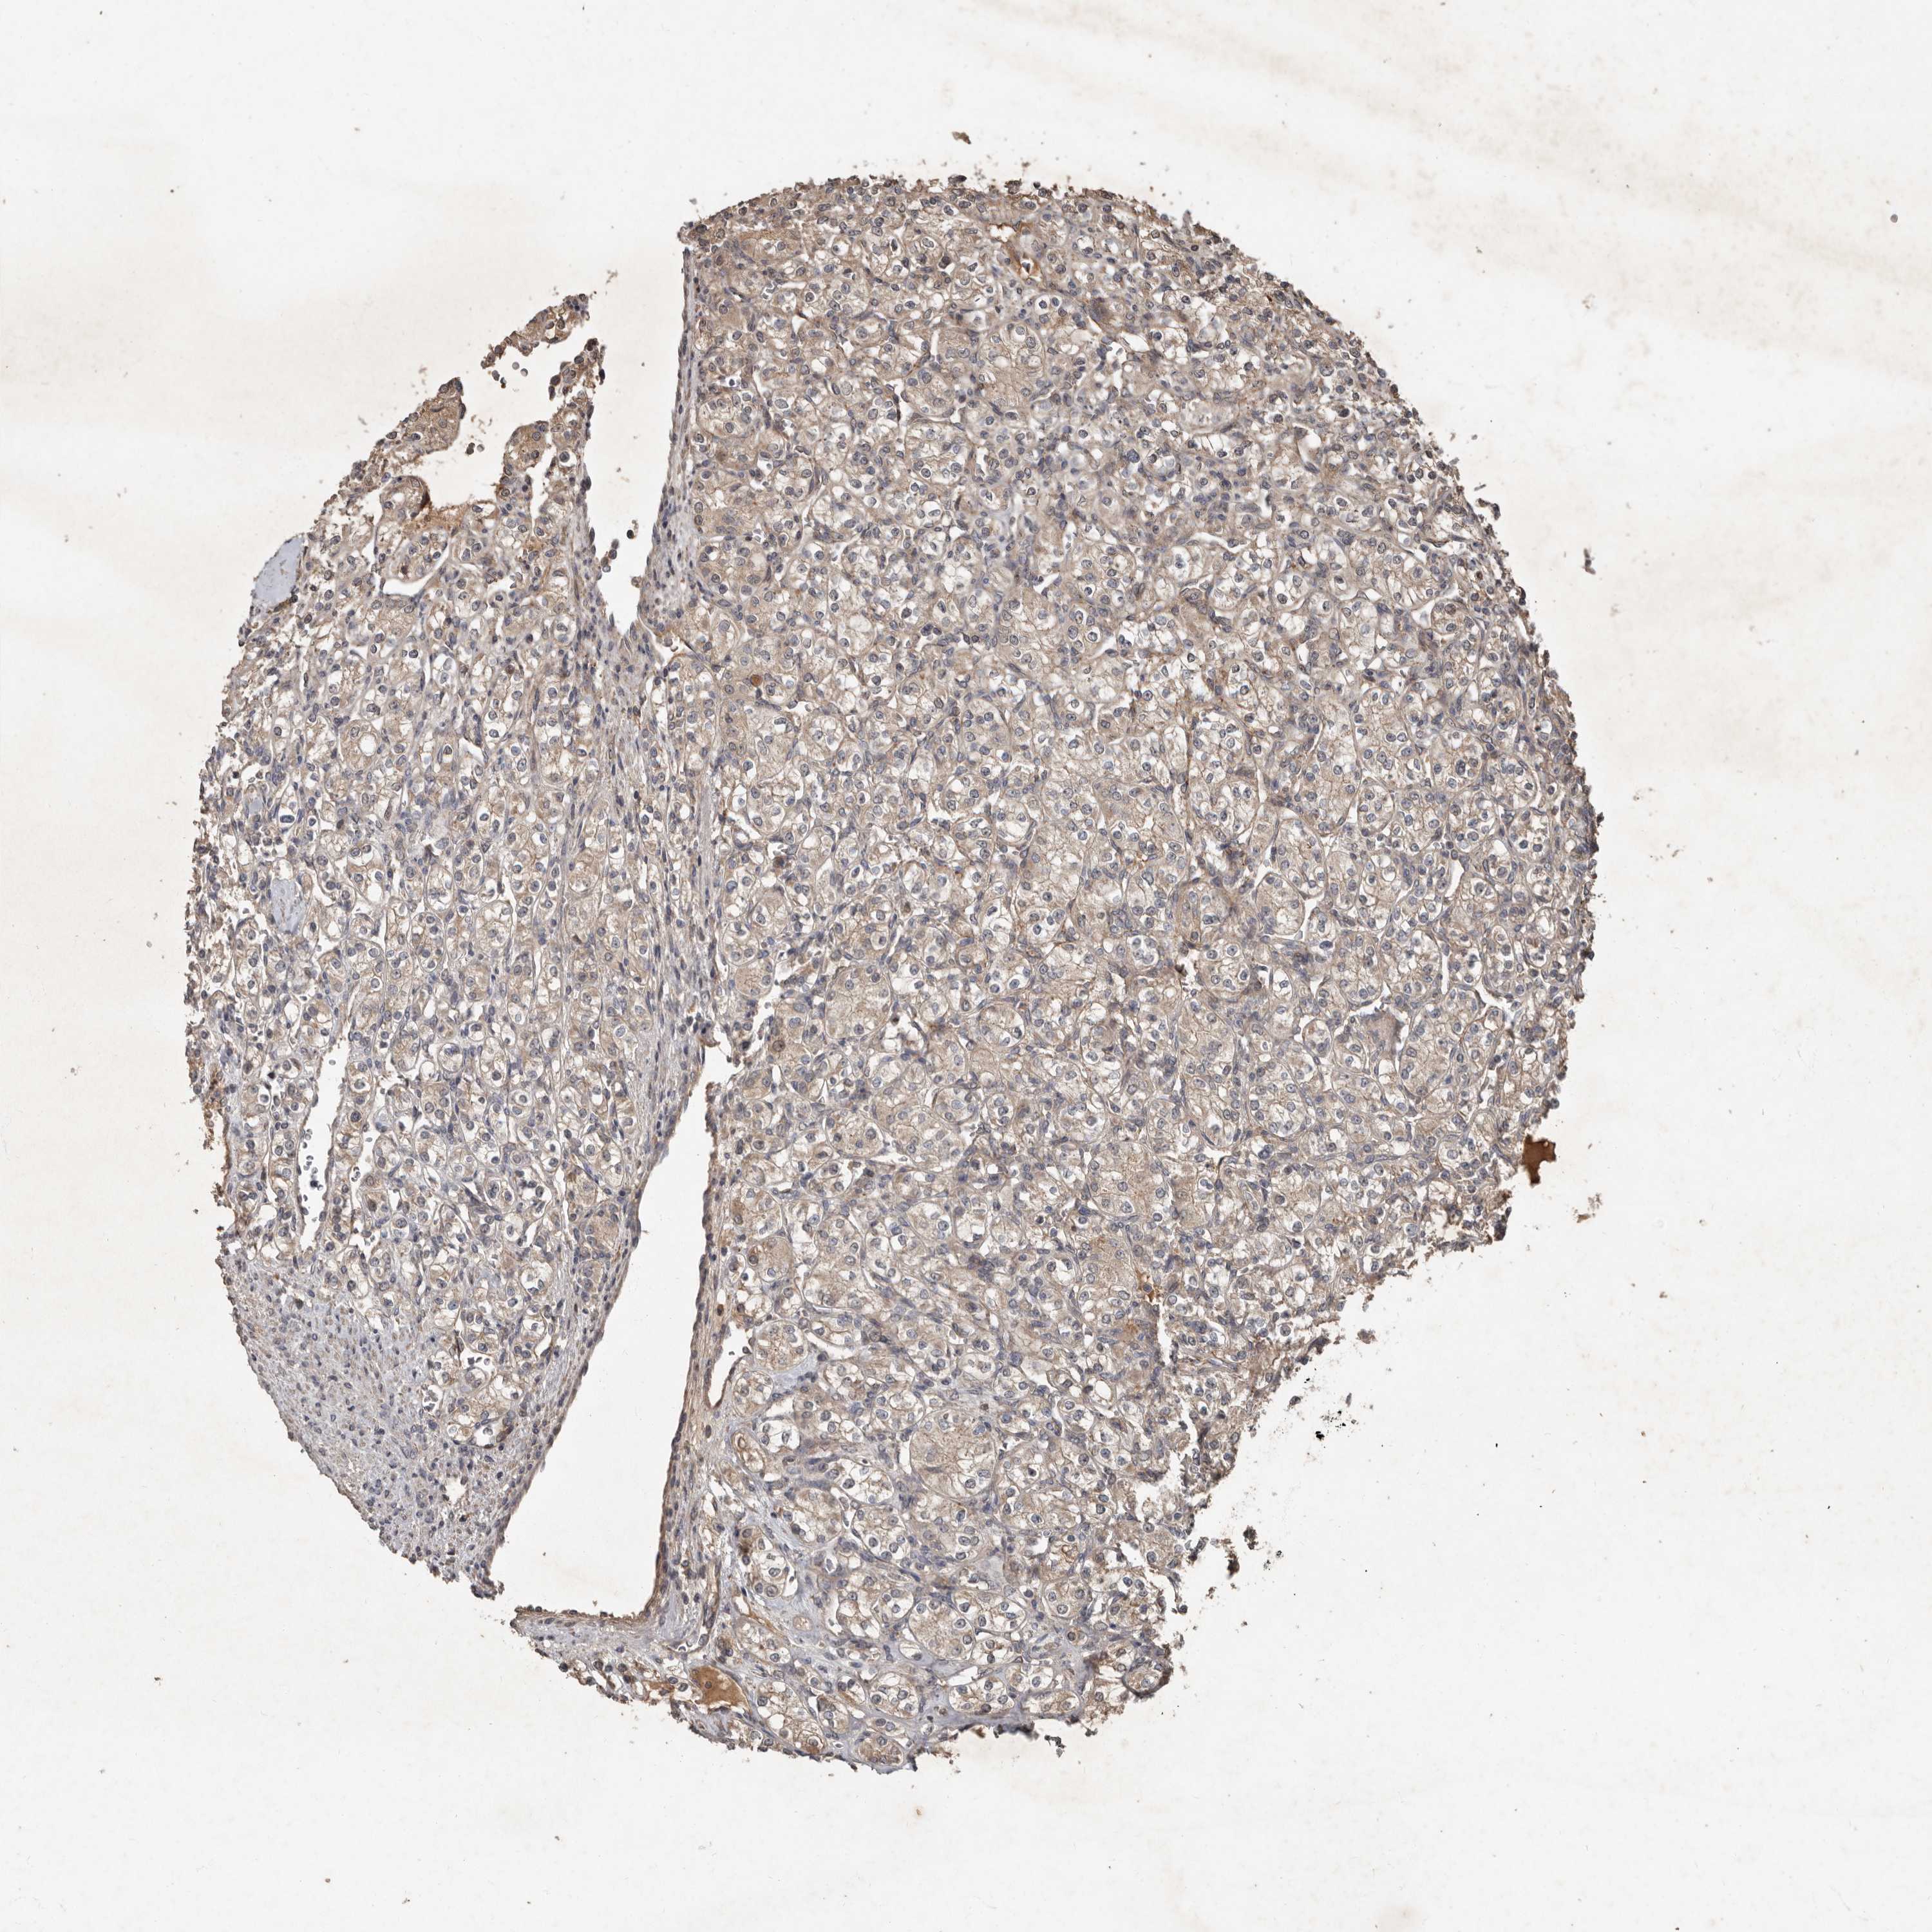

KIDNEY RENAL PAPILLARY CELL CARCINOMA (TCGA) - Interactive survival scatter ploti

The Survival Scatter plot shows the clinical status (i.e. dead or alive) for all individuals in the patient cohort, based on the same data that underlies the corresponding Kaplan-Meier plots. Patients that are alive at last time for follow-up are shown in blue and patients who have died during the study are shown in red.

The x-axis shows the expression levels (FPKM) of the investigated gene in the tumor tissue at the time of diagnosis. The y-axis shows the follow-up time after diagnosis (years). Both axes are complimented with kernel density curves demonstrating the data density over the axes. The top density plot shows the expression levels (FPKM) distribution among dead (red) and alive patients (blue). The right density plot shows the data density of the survived years of dead patients with high and low expression levels respectively, stratified using the cutoff indicated by the vertical dashed line through the Survival Scatter plot. This cutoff is automatically defined based on the FPKM cutoff that minimizes the p-score. The cutoff can be changed by dragging the vertical line or by entering a cutoff value in the square labeled "Current cut-off".

Under the Survival Scatter plot the p-score landscape (black curve; left axis) is shown together with dead median separation (red curve; right axis). Dead median separation is the difference in median mRNA expression between patients who have died with high and low expression, respectively. It is calculated as follows: median FPKM expression of dead patients with high expression - median FPKM expression of dead patients with low expression. This is intended to aid the user in visually exploring custom cutoffs and the associated p-scores and dead median separation.

Individual patient data is displayed and can be filtered by clicking on one or more of the category buttons on the top of the page. Categories describing expression level and patient information include: high, low, alive, dead, female, male and tumor stages. The scale of the x-axis can be toggled between linear and log-scale by clicking on the "x log" button. Mouse-over function shows TCGA ID, patient information and mRNA expression (FPKM) for each patient.

& Survival analysisi

Kaplan-Meier plots summarize results from analysis of correlation between mRNA expression level and patient survival. Patients were divided based on level of expression into one of the two groups "low" (under cut off) or "high" (over cut off). X-axis shows time for survival (years) and y-axis shows the probability of survival, where 1.0 corresponds to 100 percent.

KIF26B is not prognostic in Kidney Renal Papillary Cell Carcinoma (TCGA)